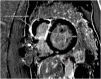

"Cases of SCMR" is a case series on the SCMR website (https://www.scmr.org) for the purpose of education. The cases reflect the clinical presentation, and the use of cardiovascular magnetic resonance (CMR) in the diagnosis and management of cardiovascular disease. The 2022 digital collection of cases are presented in this manuscript.

Keywords: Arrhythmogenic cardiomyopathy; COVID-19; Cardio-oncology; Congenital Heart disease; Coronary artery aneurysm; Hydatid disease; Hypertrophic cardiomyopathy; Metastatic disease; Myocardial. infarction; Myocarditis; Takotsubo; Vaccine associated myocarditis; Viability.